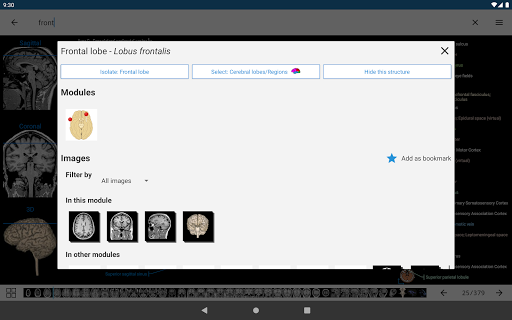

e-Anatomy memiliki lebih dari 26.000 gambar yang berisi serangkaian gambar dalam tampilan aksial, koronal, dan sagital serta radiografi, angiografi, gambar diseksi, bagan anatomi, dan ilustrasi. Semua gambar medis diberi label dengan cermat, lebih dari 967.000 label tersedia dalam 12 bahasa termasuk Terminologia Anatomica Latin.

- Ketuk label untuk menampilkan struktur anatomi

*Peningkatan tampilan detail bagian anatomi untuk memudahkan identifikasi dalam gambar modul saat ini dan modul lainnya.

-Dalam tampilan detail struktur anatomi , pin sekarang menunjukkan struktur terkait di semua gambar yang ada

- "Filter oleh", dalam tampilan detail Anda sekarang dapat menyaring gambar yang mengandung struktur anatomi oleh modalitas